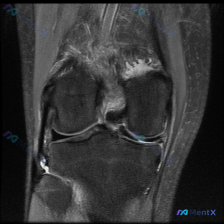

刚整理了一份膝关节MRI的读片思路,分享给大家,病例核心问题是「影像中观察到了什么异常,尤其是半月板异常」,先给大家理清楚整个分析过程。 一、影像基本信息 这是一张膝关节冠状位T2序列MRI,我们先梳理所有可见的异常信息: 1. 骨骼: 股骨外侧髁、胫骨外侧平台可见弥漫性T2高信号,提示骨髓水肿/骨...

今天整理了一份膝关节MRI读片病例,针对提问的半月板异常做了完整分析,分享给大家一起参考。 病例影像基础信息 这是一份膝关节MRI冠状位T2加权影像,针对半月板异常做系统评估: 影像发现整理 1. 骨性结构:股骨远端、胫骨近端骨皮质连续,无骨折或骨质破坏;胫骨平台外侧可见局限性T2高信号,提示骨髓水...

整理了一份很有警示意义的膝关节MRI读片病例,分享一下我的分析思路。 病例影像基础信息 这是一张膝关节冠状位T2加权脂肪抑制序列MRI影像,核心提示是存在半月板异常,我们来看具体的影像学发现: 1. 骨骼结构:股骨外侧髁、胫骨外侧平台可见大片弥漫性信号增高,这是典型的骨髓水肿表现,信号边界符合骨髓水...